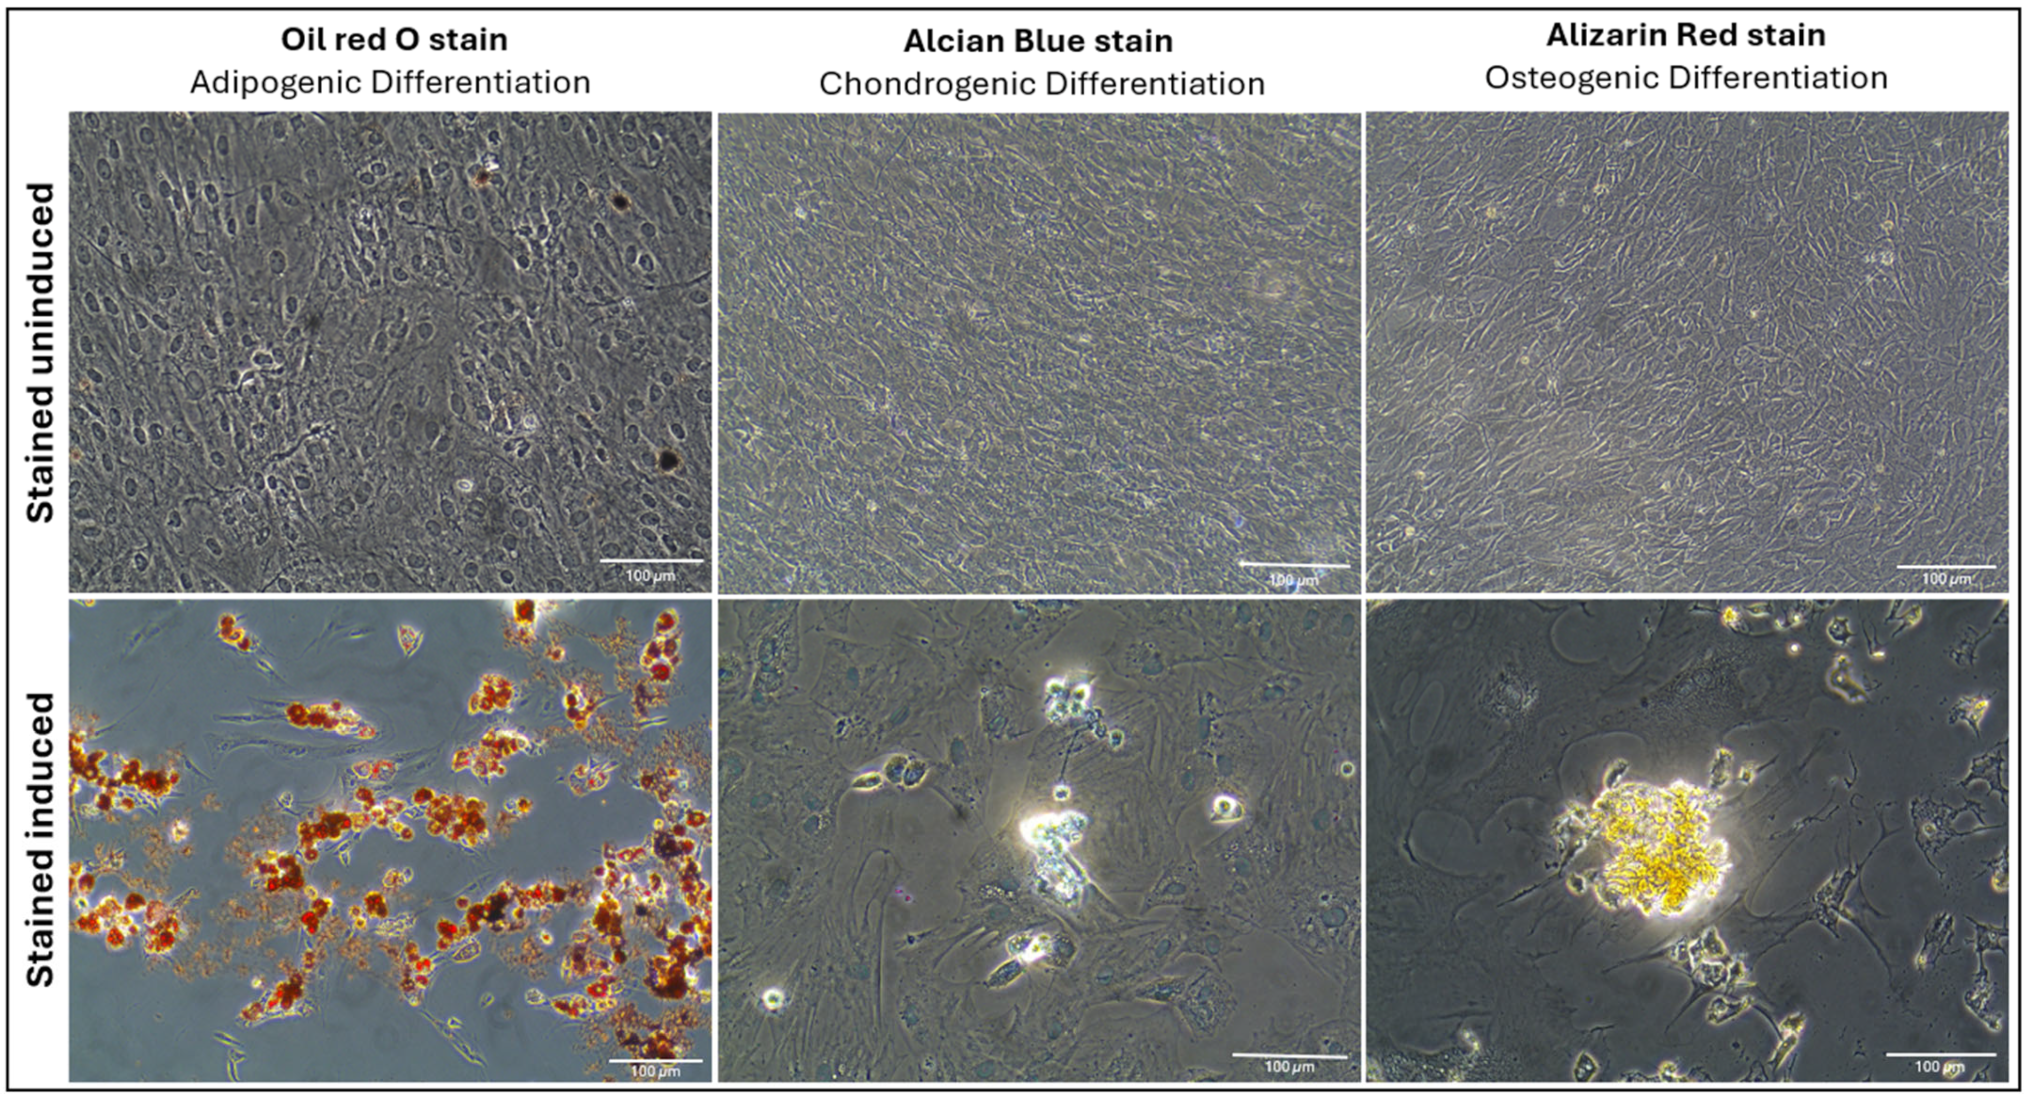

2.1.3. Multilineage Differentiation

4.4. Multilineage Differentiation Assessment of AD-MSCs

4.4.1. Adipogenic Differentiation

4.4.2. Chondrogenic Differentiation

4.4.3. Osteogenic Differentiation